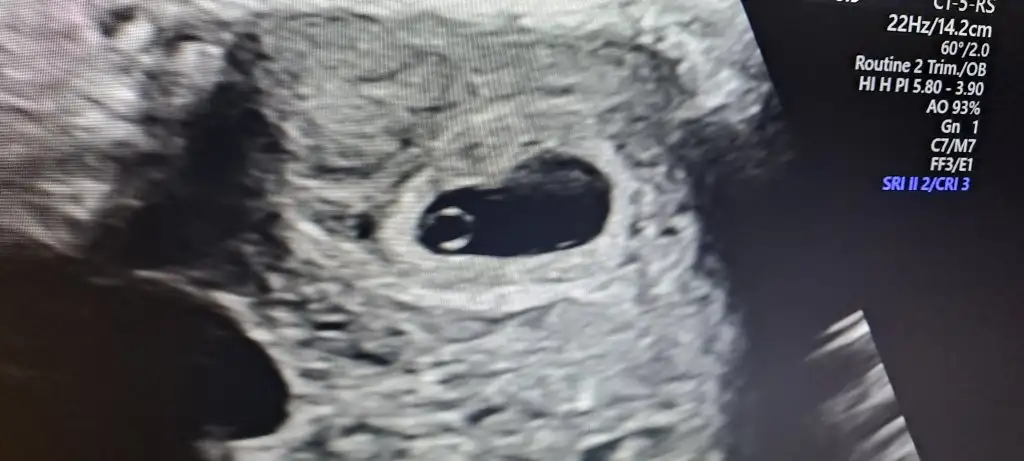

Kızlar devlete gittim kesem içinde bebeğim gözüktü kalp atışına 10 gün sonra gel dedi ama ben bugün öğlen sonu özele de gidicem artık oraya gideceğim için başlangıcı yaptircam fasulye gibi kesesi ya

Maşallah gözün aydın canım darısı başıma benden de bugün kan aldılar artışa bakılacak sanırım ona göre bakarız keseye dedi sende sadece kesemi gözuktü bebekte varmıydı